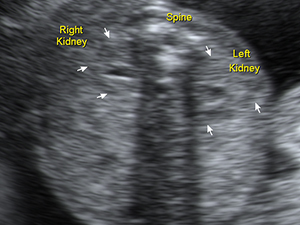

Two fetal kidneys Heart